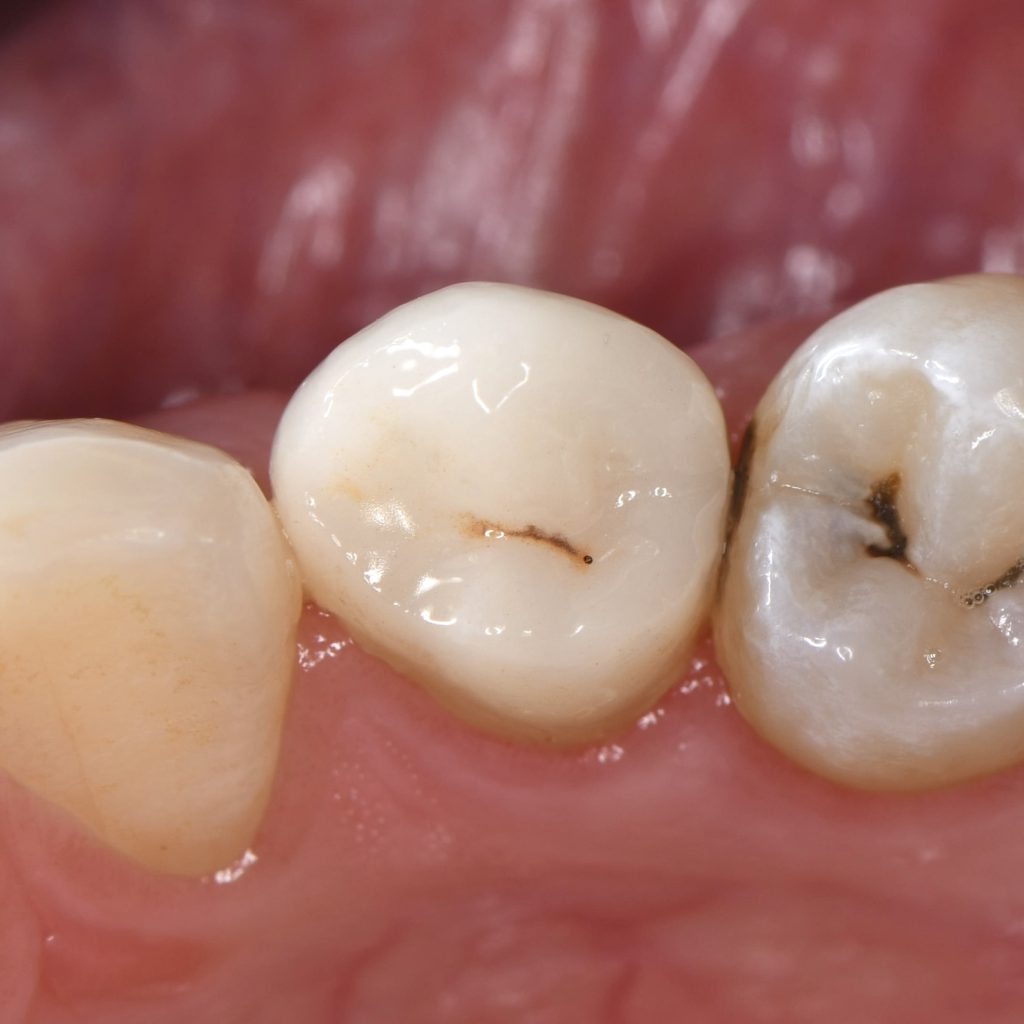

Initial situation

Occlusal view